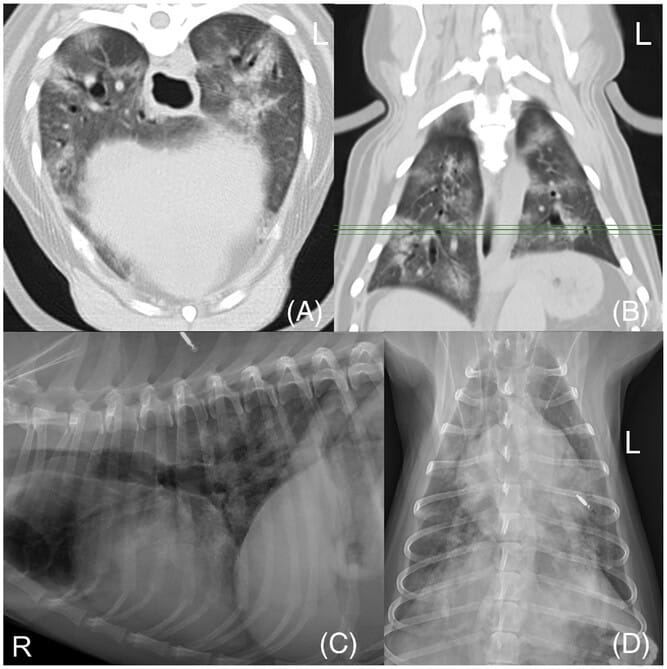

Nine-year-old female, spayed Chihuahua, acute on chronic tachypnea; history stated “suspect PTE”. The imaging and history can be used as an example of major misinterpretation due to framing bias; the imaging also illustrates the challenges of diagnosing ILD, even with the addition of CT. Transverse (A) and dorsal (B) CT images show multifocal unstructured interstitial to alveolar lung pattern that is somewhat wedge-shaped as it extends to the lung periphery. Right lateral (C) and ventrodorsal (D) radiographs show multifocal lung disease as well as enlarged pulmonary arteries caudodorsally. PTE was prioritized for the combination of findings. Histopathologic diagnosis revealed ILD, to include cryptogenic organizing pneumonia and secondary diffuse alveolar damage. Embolic processes were not identified. Image acquisition parameters for CT: standard reconstruction kernel, WW:1500, WL:−600, 2 mm slice thickness. ILD, interstitial lung disease.